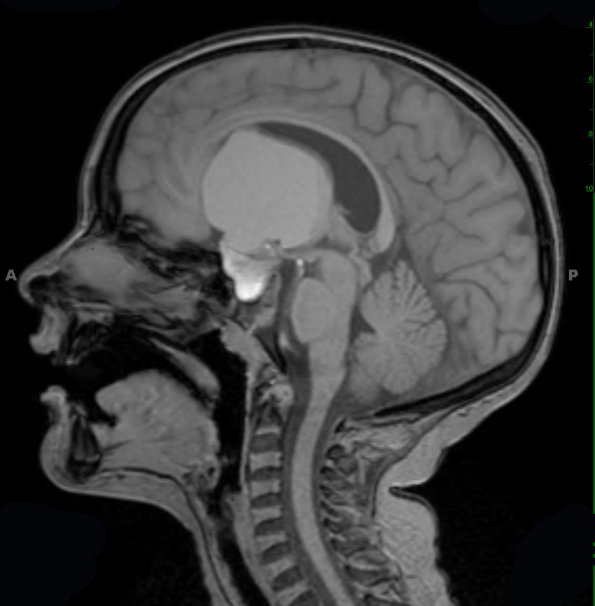

Case 11 History ---- The patient is a seven-year-old boy with short stature and a two-week history of increasing headaches. MRI in February 2011 showed a 5.6 x 4.7 x 4.9 cm mass. Clinical impression: Craniopharyngioma. Operative procedure: Craniotomy for resection. ---- 11A1-4 Multiple MRI scans show a peripherally rim-enhancing, cystic sellar/suprasellar mass with a proteinaceous/hemorrhagic fluid level, centered in the sella/suprasellar region, with expansion of the sella. This T1-weighted scan is shown in sagittal (11A1) and axial (11A2) scans demonstrating the size and effect the mass has on the ventricular systems.